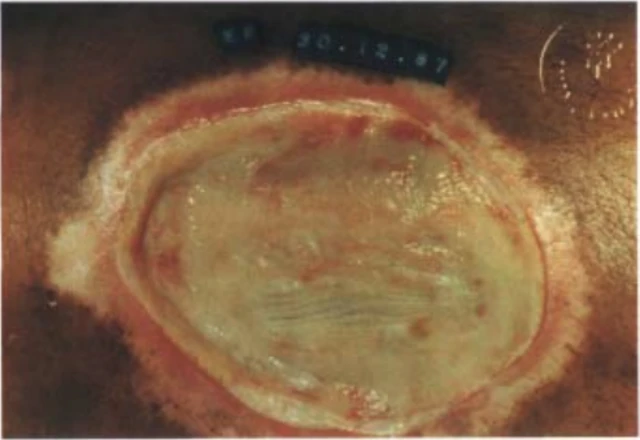

สัปดาห์ต่อมา เขาอยู่ในห้องรักษาผู้ป่วยวิกฤตของโรงพยาบาลในนครริโอ เด จาเนโร ด้วยอาการปวดหัว วิงเวียนศีรษะ อาเจียน ปวดบวมตามร่างกาย ขาบวมแดงหนัก จนศัลยแพทย์ต้องกรีดเนื้อตายออกมา

ฟาเบียโน ไม่ได้เจ็บป่วยในลักษณะนี้เพียงคนเดียว แต่มีอีก 13 คน ที่เคยได้สัมผัสใกล้ชิดกับหินเรืองแสง แต่ต่อมาต้องเข้าห้องไอซียู และไม่กี่วันต่อมา มีคนเสียชีวิต 4 คน รวมถึงหลานสาวของเฟอร์เรียรา ชื่อ ลีเด เฟอร์เรียรา